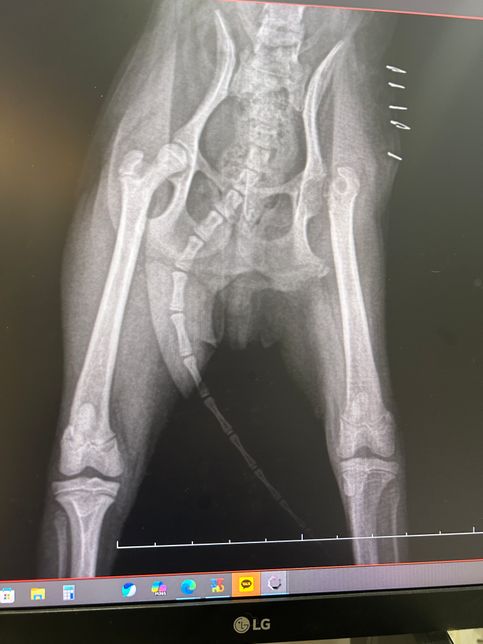

- 반려동물 건강반려동물Q. 대퇴골두 상태좀 봐주시겠어요? 부탁해요지난번 오른쪽 대퇴골두 절단술 받았습니다엑스레이상 반대쪽도 혹시 의심 소견 있을까요? ㅠㅠ의견 주세여 부탁드려요~~!!!!